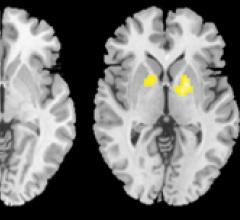

September 8, 2014 — Brain iron levels offer a potential biomarker in the diagnosis of attention deficit hyperactivity disorder (ADHD) and may help physicians and parents make better-informed treatment decisions, according to new research published online in the journal Radiology.

May 2, 2014 — A new study has found that children and adolescents with attention deficit hyperactivity disorder (ADHD) have disrupted connections between different areas of the brain that are evident on resting-state functional magnetic resonance imaging (rfMRI). The results of this research are published online in the journal Radiology.